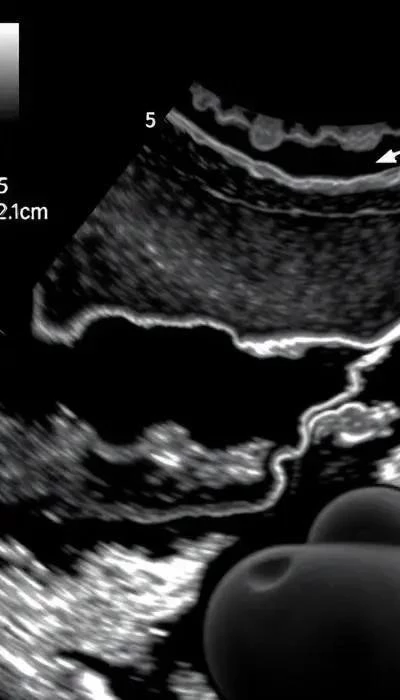

Второй скрининг УЗИ, проводимый в период с 18 по 22 неделю беременности, направлен на детальную оценку анатомического строения плода. На этом сроке органы и системы плода достаточно развиты, чтобы их можно было тщательно изучить с помощью ультразвука. Основная цель – выявление возможных пороков развития.

Во время второго УЗИ врач оценивает состояние головного мозга, сердца, почек, желудочно-кишечного тракта и других органов плода. Оценивается длина костей, размеры органов и их соответствие гестационному сроку. Также, если положение плода позволяет, можно определить пол ребенка. Врач также оценивает состояние плаценты и околоплодных вод.